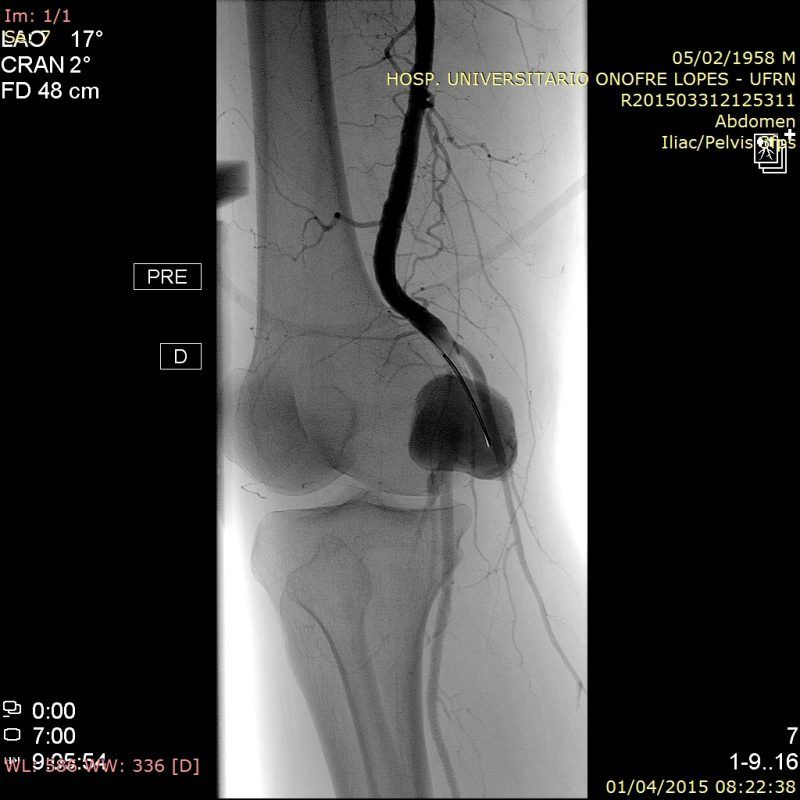

Paciente do sexo masculino com grande aneurisma da artéria Poplítea direita.

Apresentava queixas de dor e edema na perna. Os sintomas dolorosos estão relacionados à compressão do nervo poplíteo enquanto o edema é devido à compressão da veia poplítea (podendo levar a sua trombose).

O tratamento escolhido foi o implante de stent revestido 7×40 devido ao menor calibre da artéria poplítea distal ao aneurisma. Contudo, o stent apresentou endoleak mesmo após a acomodação com balão 7×40. Assim, um stent mais calibroso e longo (9×15) foi implantado a partir da secção mais dilatada do stent 7×40, tendo eliminado o endoleak e excluído o aneurisma.

O procedimento foi realizado por via percutânea através da femoral esquerda com introdutor 9F.